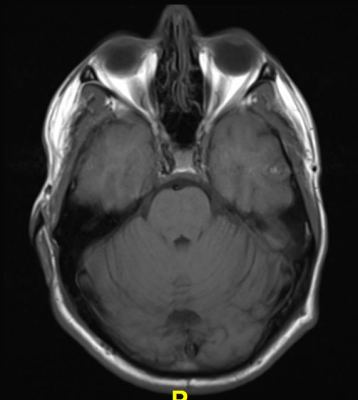

December 10, 2019 — Magnetic resonance imaging (MRI) illuminates abnormalities in the brains of people with depression, potentially opening the door to new and improved treatments for the disorder, according to two studies presented in December the annual meeting of the Radiological Society of North America (RSNA).

Wengler and colleagues at the Renaissance School of Medicine at Stony Brook University in Stony Brook, N.Y., recently studied connections between MDD and disruptions in the blood-brain barrier (BBB), a network of blood vessels and tissue that protects the brain from foreign substances. Using a new MRI technique they developed called intrinsic diffusivity encoding of arterial labeled spins (IDEALS), they looked at BBB water permeability, or the movement of water out of the blood vessels and into the brain tissue.

Comparison of results in 14 healthy individuals and 14 MDD patients found that less water moved from inside the blood vessels to outside in the MDD patients, representing disrupted BBB integrity. This difference was particularly large in two regions of the brain: the amygdala and the hippocampus.

A second study presented at RSNA 2019 looked at abnormalities in the complex network of connections in the brain known as the connectome for their role in depression. Previous research has focused on characterizing the connections between different brain regions, but this study, from researchers at the University of North Carolina (UNC) in Chapel Hill, N.C., looked deeper within individual brain regions.

The researchers compared 66 adults with MDD and 66 matched healthy controls during wakeful rest using functional MRI (fMRI) and a newly developed multiscale neural model inversion framework that linked the brain's microscopic circuitry with its larger-scale interactions. As part of the study, the researchers were able to assess excitatory or inhibitory influence between neuronal cell groups. A proper balance between excitation and inhibition is crucial to a well-functioning brain.

Patients with MDD had abnormal patterns of excitation and inhibition at the dorsal lateral prefrontal cortex, a brain area important to cognitive control functions, including the regulation of the amygdala, a key region embedded deep in the brain for expression of emotion. It has long been hypothesized that malfunctioning inhibitory control over the amygdala could result in depressive symptoms.